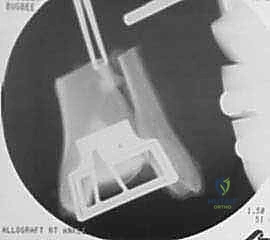

2. Talar Graft Preparation:

* The talus graft is typically cut freehand using an oscillating saw. The cut is made at the interface between the anterior neck and the articular cartilage.

3. Graft Lavage: Once both the tibial and talar grafts are prepared, we routinely perform copious lavage of both grafts. This step is critical to remove immunogenic marrow elements, potentially reducing the host inflammatory response and improving graft incorporation.

- With the ankle held in a position of plantarflexion, carefully introduce and seat the prepared tibial allograft onto the resected tibial plafond. Ensure it sits flush and stable.

- Next, introduce and seat the talar allograft onto the resected talar dome.